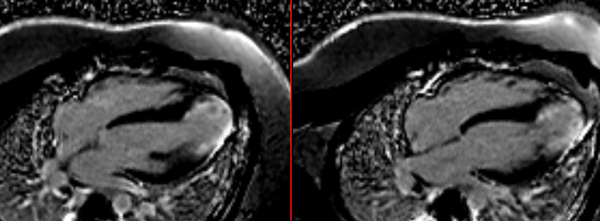

A complex long-standing, slow growing LV aneurysm